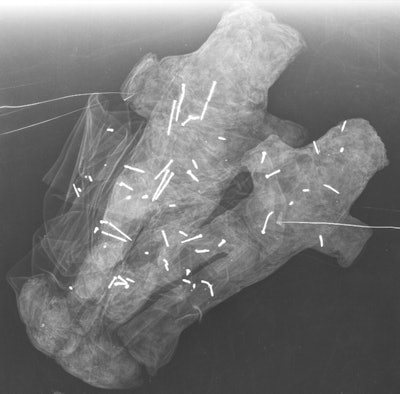

Finally, the paired dolls were not clearly identifiable as male or female, they wrote. The fact that they are a duo could signify a couple, a father and son, or siblings. The researchers found 58 needles in these two dolls: 20 in the white doll, 33 in the black doll, and five scattered across the fabric of each.

Cracking the code

Questions remain about the dolls' meaning, according to the team.

"The radiographic analysis raised questions ... about the evil role of each doll and the meaning of the fabric used," the authors wrote. "Were [the dolls] bewitched and not used, or were they made in order to harm and not to kill?"